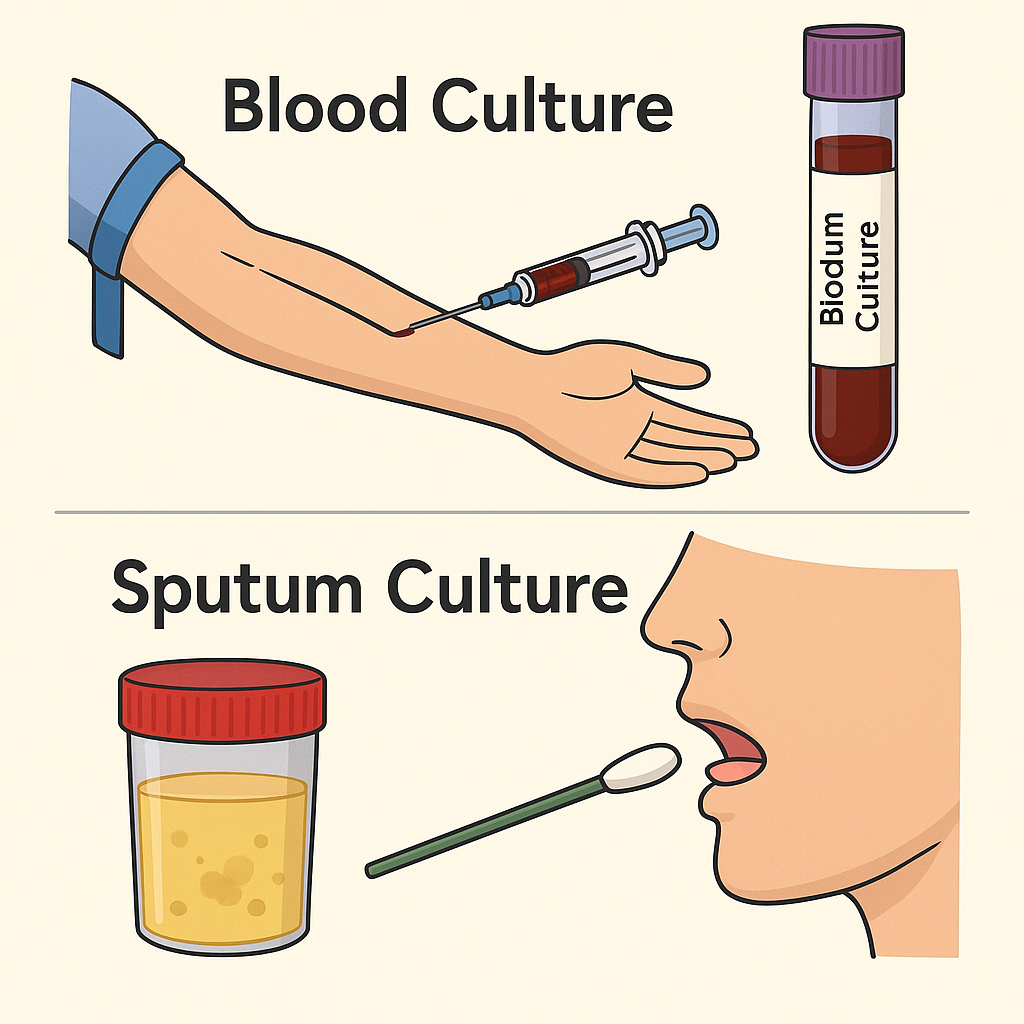

Culture (કલ્ચર):

- કલ્ચરલ ટેસ્ટમાં બ્લડ કલ્ચર અને સ્ફુટમ કલ્ચર કરવામાં આવે છે. જેથી તેમાં ક્યાં પ્રકારના માઇક્રો ઓર્ગેનિઝમ રહેલ છે તે આઇડેન્ટિફાય કરી શકાય છે

Sputum studies (સ્ફુટમ સ્ટડી):

- સ્ફુટમ સ્ટડીમાં સ્ફુટમ (મ્યુકસ કફ) ની સ્ટડી કરવામાં આવે છે. જેથી સ્ફુટમમાં રહેલ બેક્ટેરીયા, વાયરસ અને એબનોર્મલ સેલને આઇડેન્ટીફાય કરી શકાય. સ્ફુટમ સ્ટડીની મદદથી ન્યુમોનિયા, ટયૂબરક્યુલોસિસ જેવી કન્ડીશનને આઇડેન્ટીફાય કરી શકાય.